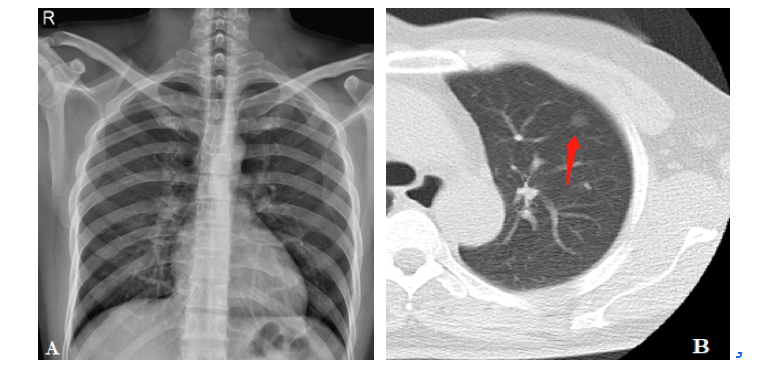

患者女,54岁,健康体检。图A为X线胸片,肺部未见明确异常;图B为胸片当天胸部低剂量螺旋CT扫描肺窗,右上肺见磨玻璃结节影(箭头)